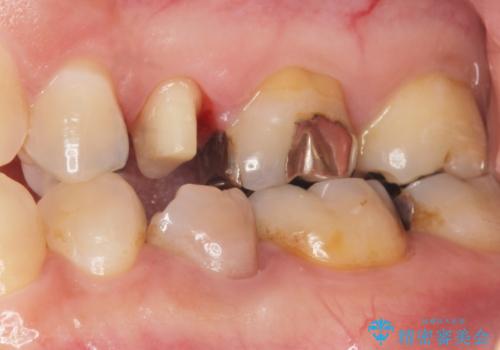

歯ぐきを押すと痛い 神経が死んでいる歯の治療 40代女性

- 歯の根のあたりの歯ぐきを押すと痛むことを主訴に来院された患者様です。

精査したところ、左上の小臼歯(左上5)の神経が死んでいました。

根管治療後、セラミッククラウンによる補綴を行いました。